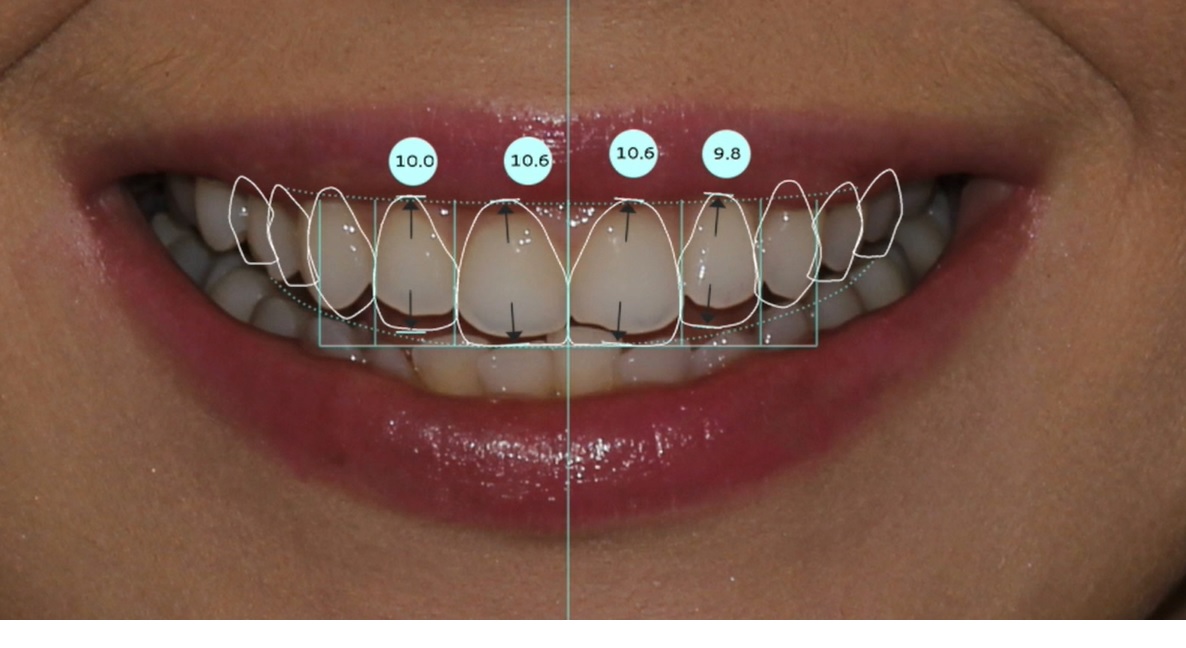

Belirlenen yeni diş yapısı ve dental oranlara göre gülüş tasarım yazılımı, planlanan tedavinin bitmiş halinin sanal görüntüsünü oluşturur. Bu görüntü üzerinde, hastanın da istek ve düşünceleri dikkate alınarak gerekli düzeltmeler yapılır.

Son hali verilen dijital gülüş tasarımı üzerinde dijital ölçümler yapılarak veya doğrudan Cad-Cam cihazlar kullanılarak dijital planlama , Mock-up adı verilen reel tasarıma dönüştürülür. Daha sonra, Mock-up tasarım, ağıza aktarılarak geçici dişler üretilir. Bu aşamada , yüz-dudak ve alt-üst dişlerin birbirleriyle uyumları ile diş renk ve boyutları, dişeti konturları detaylı olarak tekrar değerlendirilir. Bu değerlendirmeler sonrasında Mock-up üzerinde gerekli son düzenlemeler yapılıp protetik işlemlere geçilir. Bu iş akışı neticesinde elde edilen estetik sonuç, dijital tasarım ve Mock-up çalışması ile oldukça uyumludur.